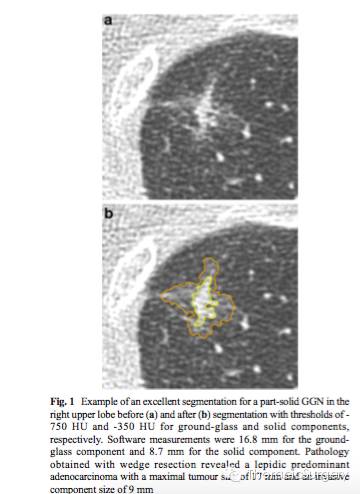

近年来肺部早期肺癌的发病率越来越高,其中亚实性肺结节为其主要亚型。对于亚实性肺结节成份的准确评估有助于术前诊断肺癌的病理亚型,从而知道临床决策。但是,对于亚实性肺结节精确测量并非易事。为了评估CT软件在分割亚实性肺腺癌的毛玻璃影和实性成份中的作用,来自韩国的Jin Mo Goo等开展了一项研究,研究结果发表在近期的Eur Radiol杂志上。

该研究中共有73例表现为亚实性结节的肺腺癌患者纳入研究。两位有经验的放射学家测定肺窗下毛玻璃影的最大直径,以及肺窗和纵隔窗下实性成份的最大直径。研究者使用软件在肺窗和纵隔窗分别采用5(-850HU to -650 HU)和9(-130 HU to -500 HU)个衰减阈值对结节进行成份分割。同时研究者比较常规方案和应用软件测量的毛玻璃影和实性成份,与病理测量的肿瘤大小和浸润性成分的相关性。

研究者发现,-750HU阈值时软件在肺窗测量的毛玻璃成分与病理测量的肿瘤大小无明显差异,平均为+0.06mm,但是与常规的测量方案存在明显差异,平均为- 2.32mm。对于实性成分,软件测量( - 350 HU)与病理浸润性成份之间无明显差异,平均为-0.12mm,与常规测量手段(肺和纵隔窗)与病理病理浸润性成份之间肺窗下无明显差异,为0.15mm,然而在纵隔窗下存在明显差异,平均为-1.14mm。

所以,研究者认为对于亚实性肺腺癌,计算机软件测量毛玻璃影和实性成份可与病理测量相媲美。计算机软件能有效地分割亚实性结节的毛玻璃影和实性成份。同时,对于实性成份常规的影像学测量手段肺窗比纵隔窗更为准确。当然,研究者指出,该测量方案对于浸润前病变和病灶中有血管穿过的患者并不准确,且对于病理浸润成份大雨10mm的病灶也不够精确。